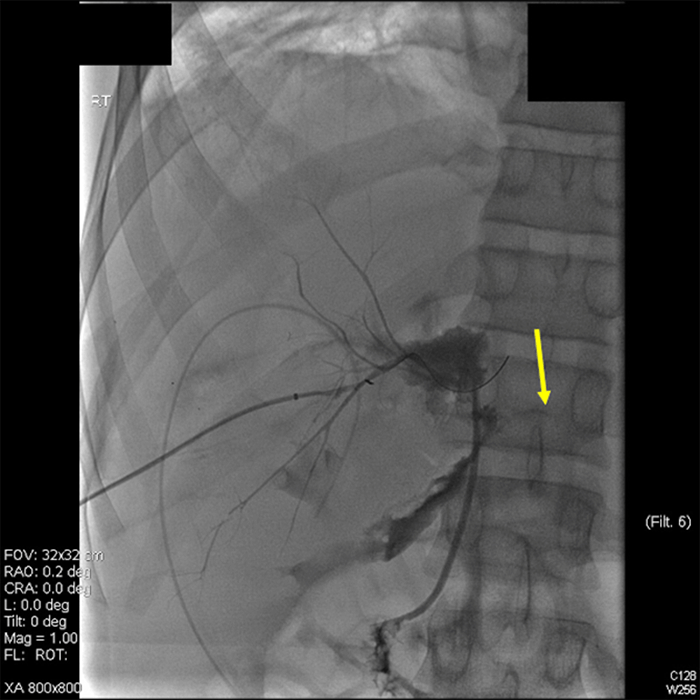

Since the patient was not showing signs of heart failure or portal hypertension, treatment of the arterioportal fistula was delayed until he was off ECMO. Before closure of the patient's abdomen, interventional radiology performed a celiac arteriogram that redemonstrated the fistula between the proximal left hepatic artery and a dilated main portal vein (Figure 2). The hepatic artery had a low bifurcation, with the left hepatic artery originating quite proximally at the level of the main portal vein injury. Due to the fistula being only 1‒2 mm distal to the origin of the left hepatic artery, it was not amendable to arterial stent-graft placement.

Figure 2. Celiac angiogram showing arterioportal fistula. Published with Permission